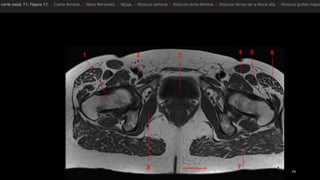

• el tensor de la fascia lata (Tfn y el

sartorio (Sa) se originan en la espina

ilíaca anterosuperior (flecha recta).

• recto femoral (Rf se origina en la

espina ilíaca anteroinferior (punta de

flecha) ,

• músculos ilíaco y psoasilíaco convergen

en un tendón común en un punto

distal que se inserta en el trocánter

menor (flecha curva).

• músculo pectíneo (Pe)

• rama superior del pubis (Pb).

• el tensorde la fascia lata (Tfn y el sartorio (Sa) se originan en la espina ilíaca anterosuperior (flecha recta). • recto femoral (Rf se origina en la espina ilíaca anteroinferior (punta de flecha) , • músculos ilíaco y psoasilíaco convergen en un tendón común en un punto distal que se inserta en el trocánter menor (flecha curva). • músculo pectíneo (Pe) • rama superior del pubis (Pb).

• músculo glúteomayor (GMa) • músculo tensor de la fascia lata (Tfl anterior y la fascia lata (FL) situada entre ambos músculos • «bandeleta de Massiat» (BM) • glúteo medio (GMe) y glúteo menor (GMI) • trocánter mayor (TM)